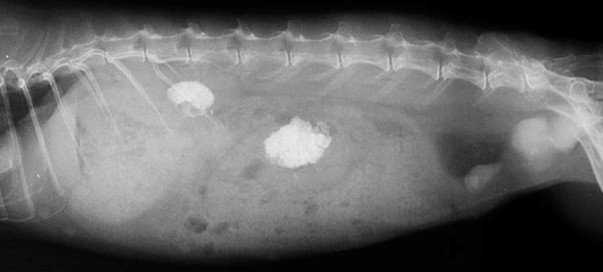

X線検査

ウサギの腎不全におけるX線検査は、腎臓(大きさ、形状、不透明度)の評価に加え、腎不全の原因や合併症(尿路結石、異所性石灰化など)を検出するためにも重要です。腎臓の大きさは病態により変化します。正常な腎臓の大きさは、第2腰椎(第2腰椎)の長さの約2.5~3倍とされますが、個体差も考慮されます。CRFでは、線維化により腎臓が萎縮し、辺縁不整を伴うことがあります。ARFでは炎症や浮腫により腎臓が腫大します。水腎症、嚢胞、腫瘍、アミロイドーシスなどでも腎腫大は見られます。腎石灰化症 腎実質へのカルシウム沈着により、腎臓のX線不透明度が増加することがあります。これは高カルシウム血症を伴う腎不全でよく見られます。腎盂や腎実質内にX線不透過性の結石が認められることもあります。進行したCRFでは、高リン血症や高カルシウム血症などにより、腎臓以外の軟部組織(胃壁、大血管壁、肺など)にカルシウムが沈着することがあります。これは重度の腎機能障害とミネラル代謝異常を示唆します。骨表面へのミネラル沈着による骨硬化症(骨密度の増加)も、進行した腎不全の所見です。